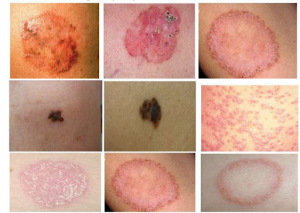

5. Skin Diseases

Skin is the largest organ of the body. Skin diseases are quite similar to seen and difficult to treat. Skin is said to be mirror of individuals internal health. In severe conditions, strong medications like steroids and immuno-suppressants are recommended by modern science that suppresses the symptoms but does not treat the cause of the disease. Dr. Vaidya expert to treat skin diseases without harming other system of the body.

Some skin diseases mention below treated by Chandigarh Ayurved Centre:-

- Eczema

- Psoriasis

- Urticaria

- Blemishes and Pigmentation

- Freckles

- Acne